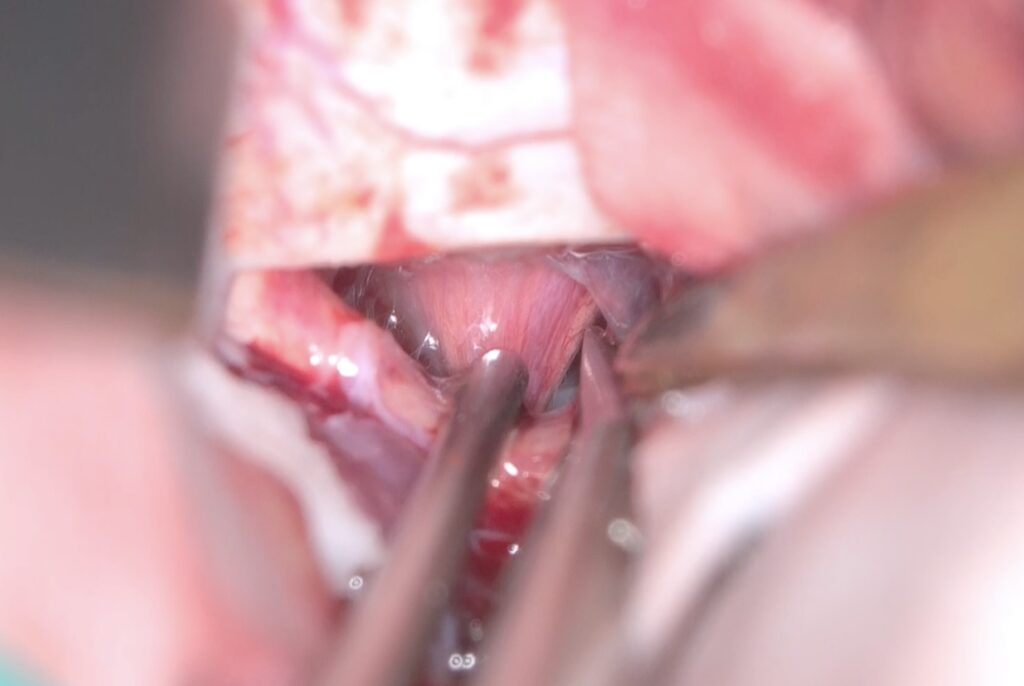

Trans-lamina terminalis approach、何度もやった古典的なアプローチです。A2と伴奏し縦走する視床下部動脈を温存して、その間隙から腫瘍を減圧していきます。

腫瘍を減圧し、最後に起こして、中脳水道や脳底動脈を確認しました。視交差の下は減圧にとどめました。